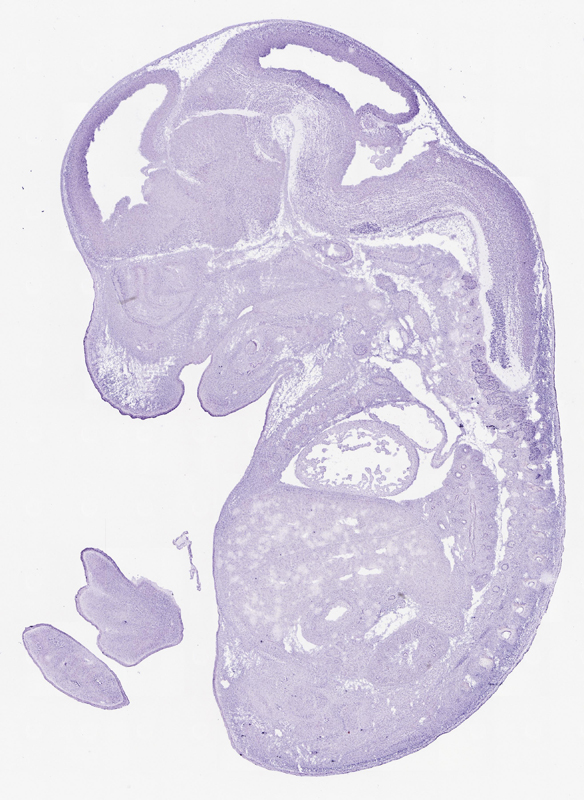

Reference: J:153498 Diez-Roux G, et al., A high-resolution anatomical atlas of the transcriptome in the mouse embryo. PLoS Biol. 2011;9(1):e1000582

Gene symbol: Tmem132e

Gene name: transmembrane protein 132E

Specimen Table S5 - Gm644: embryonic day 14.5 (more )

TS23: pons Weak

TS23: medulla oblongata Moderate

TS23: medulla oblongata basal plate Moderate Regionally restricted euxassay_000479_02 facial motor nucleus

TS23: medulla oblongata basal plate Weak Regionally restricted euxassay_000479_03 facial motor nucleus

TS23: medulla oblongata basal plate Weak Regionally restricted euxassay_000479_11 facial motor nucleus

TS23: medulla oblongata basal plate Weak Regionally restricted euxassay_000479_19 facial motor nucleus